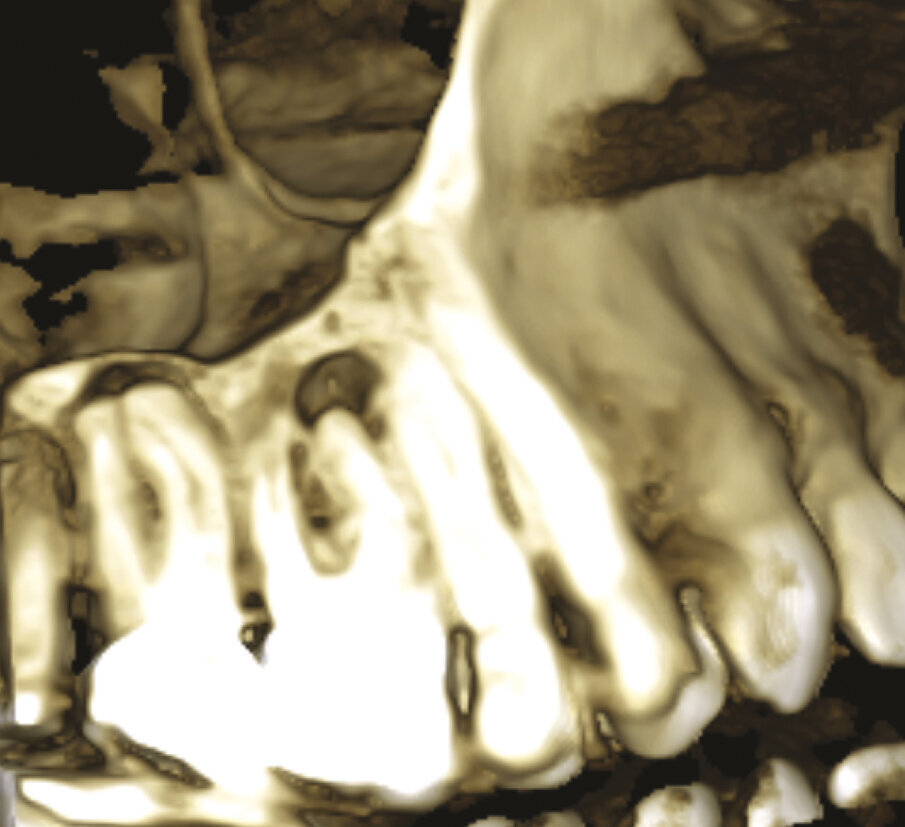

Fig. 1f, 1g - La sezione sagittale mostra ancora meglio le lesioni a carico del primo molare su entrambe le radici vestibolari e le lesioni a carico di entrambe le radici vestibolari del secondo molare, il cui canale MB1 appare completamente vuoto.